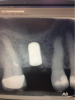

In this case, the patient’s right maxillary first molar had been extracted, and the site was grafted. The periapical radiograph taken after 6 months of healing indicated the presence of dense bone (Figure 11). There was also ample attached mucosa (Figure 12). Impressions were taken, a diagnostic cast was made, and a wax-up of the restoration was placed in the model (Figure 13). To make the radiographic guide for this case, a silicone putty index was created over the diagnostic wax-up, as described earlier. A panoramic radiograph and a CBCT scan (Figure 14) were taken with the radiographic guide in place; the guide post in the index can clearly be seen.

Fig 11. Site No. 3, 6 months after extraction and bone grafting completed.

Figure 11